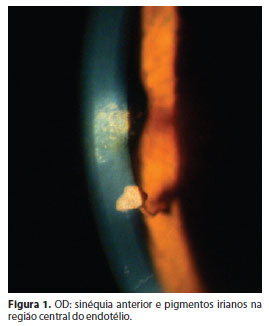

Paciente do sexo feminino, 43 anos, branca, doméstica, natural e procedente de Recife (Pernambuco), realizou primeira consulta oftalmológica com queixa de baixa acuidade visual no olho esquerdo (OE) de longa duração, com piora nos últimos 3 anos. Relatava mancha escura no OE desde criança e negava alterações ou doenças sistêmicas. Ao exame oftalmológico, apresentava acuidade visual corrigida (+3,00 ≈ -1,50 5º) de 20/30 no olho direitro (OD) e conta-dedos a 1,5 m no OE. À biomicroscopia, apresentava dermatocálase em ambos os olhos (AO), conjuntivas calmas AO; no OD, pequena sinéquia anterior, pigmentos irianos na região central do endotélio (Figura 1), câmara anterior (CA) ampla, discreta atrofia iriana com sinéquia anterior entre periferia e pupila, às 5 h (Figura 2) e discreta atrofia superior, pupila regular com reflexo fotomotor (RFM) presente e cristalino translúcido. O OE apresentava córnea com edema difuso e opacidade inferior, CA rasa, atrofia iriana e sinéquia anterior temporal e inferior, pupila irregular e corectópica (Figura 3), RFM presente e cristalino com opacificação corticonuclear incipiente. À tonometria de aplanação, pressão intraocular de 12 mmHg AO e à oftalmoscopia indireta, observava-se, no OD, disco óptico corado, com relação escavação/disco 0,2, atrofia peripapilar temporal discreta; mácula, retina e vasos sanguíneos sem alterações. No OE, foi inviável a realização deste exame, devido à opacidade corneana. À gonioscopia do OD, visualizava-se apenas a linha de Schwalbe nos quadrantes superior e nasal (grau I na classificação de Shaffer-Etienne) e linha de Schwalbe e trabeculado nos quadrantes inferior e temporal (grau II na classificação de Shaffer-Etienne), com traves iridocorneanas em todos os qua-drantes; e, no OE, havia aparente toque iridocorneano em quase toda a circunferência (grau 0 na classificação de Shaffer-Etienne), com difícil visualização por redução da transparência corneana. No exame ecográfico, não havia sinais de alterações no segmento posterior de AO.